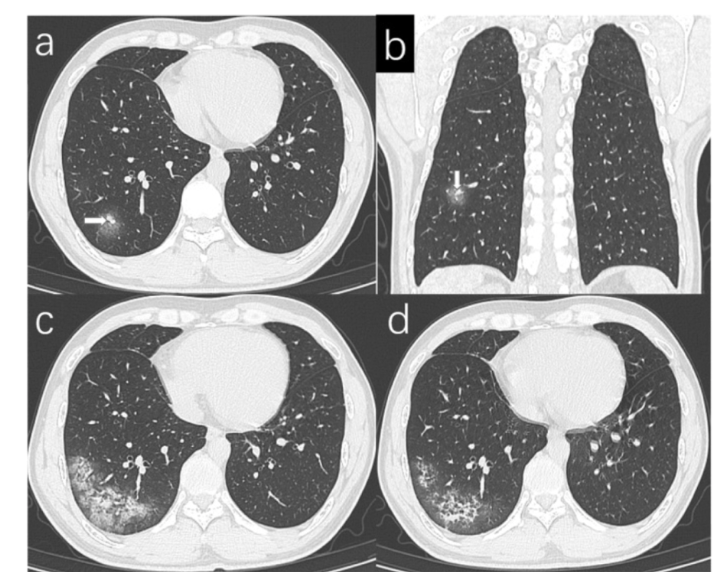

• HRCT

• Path = bronchiectasis: dilation of the bronchial wall due to chronic inflammation

• Ground glass appearance: hazy areas of increased attenuation through the lung.

• Bronchial wall thickening

49